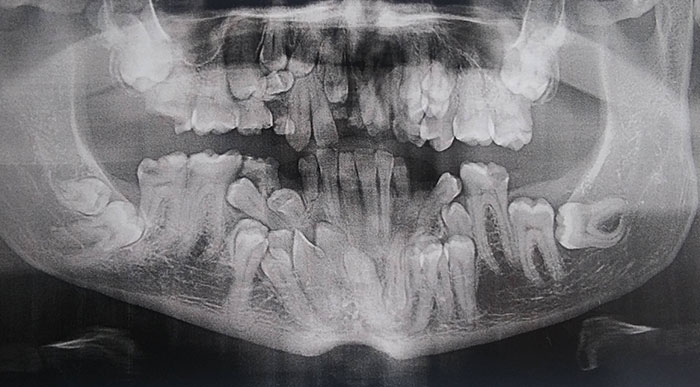

Фотографии и схемы для ОПТГ и мезиального прикуса